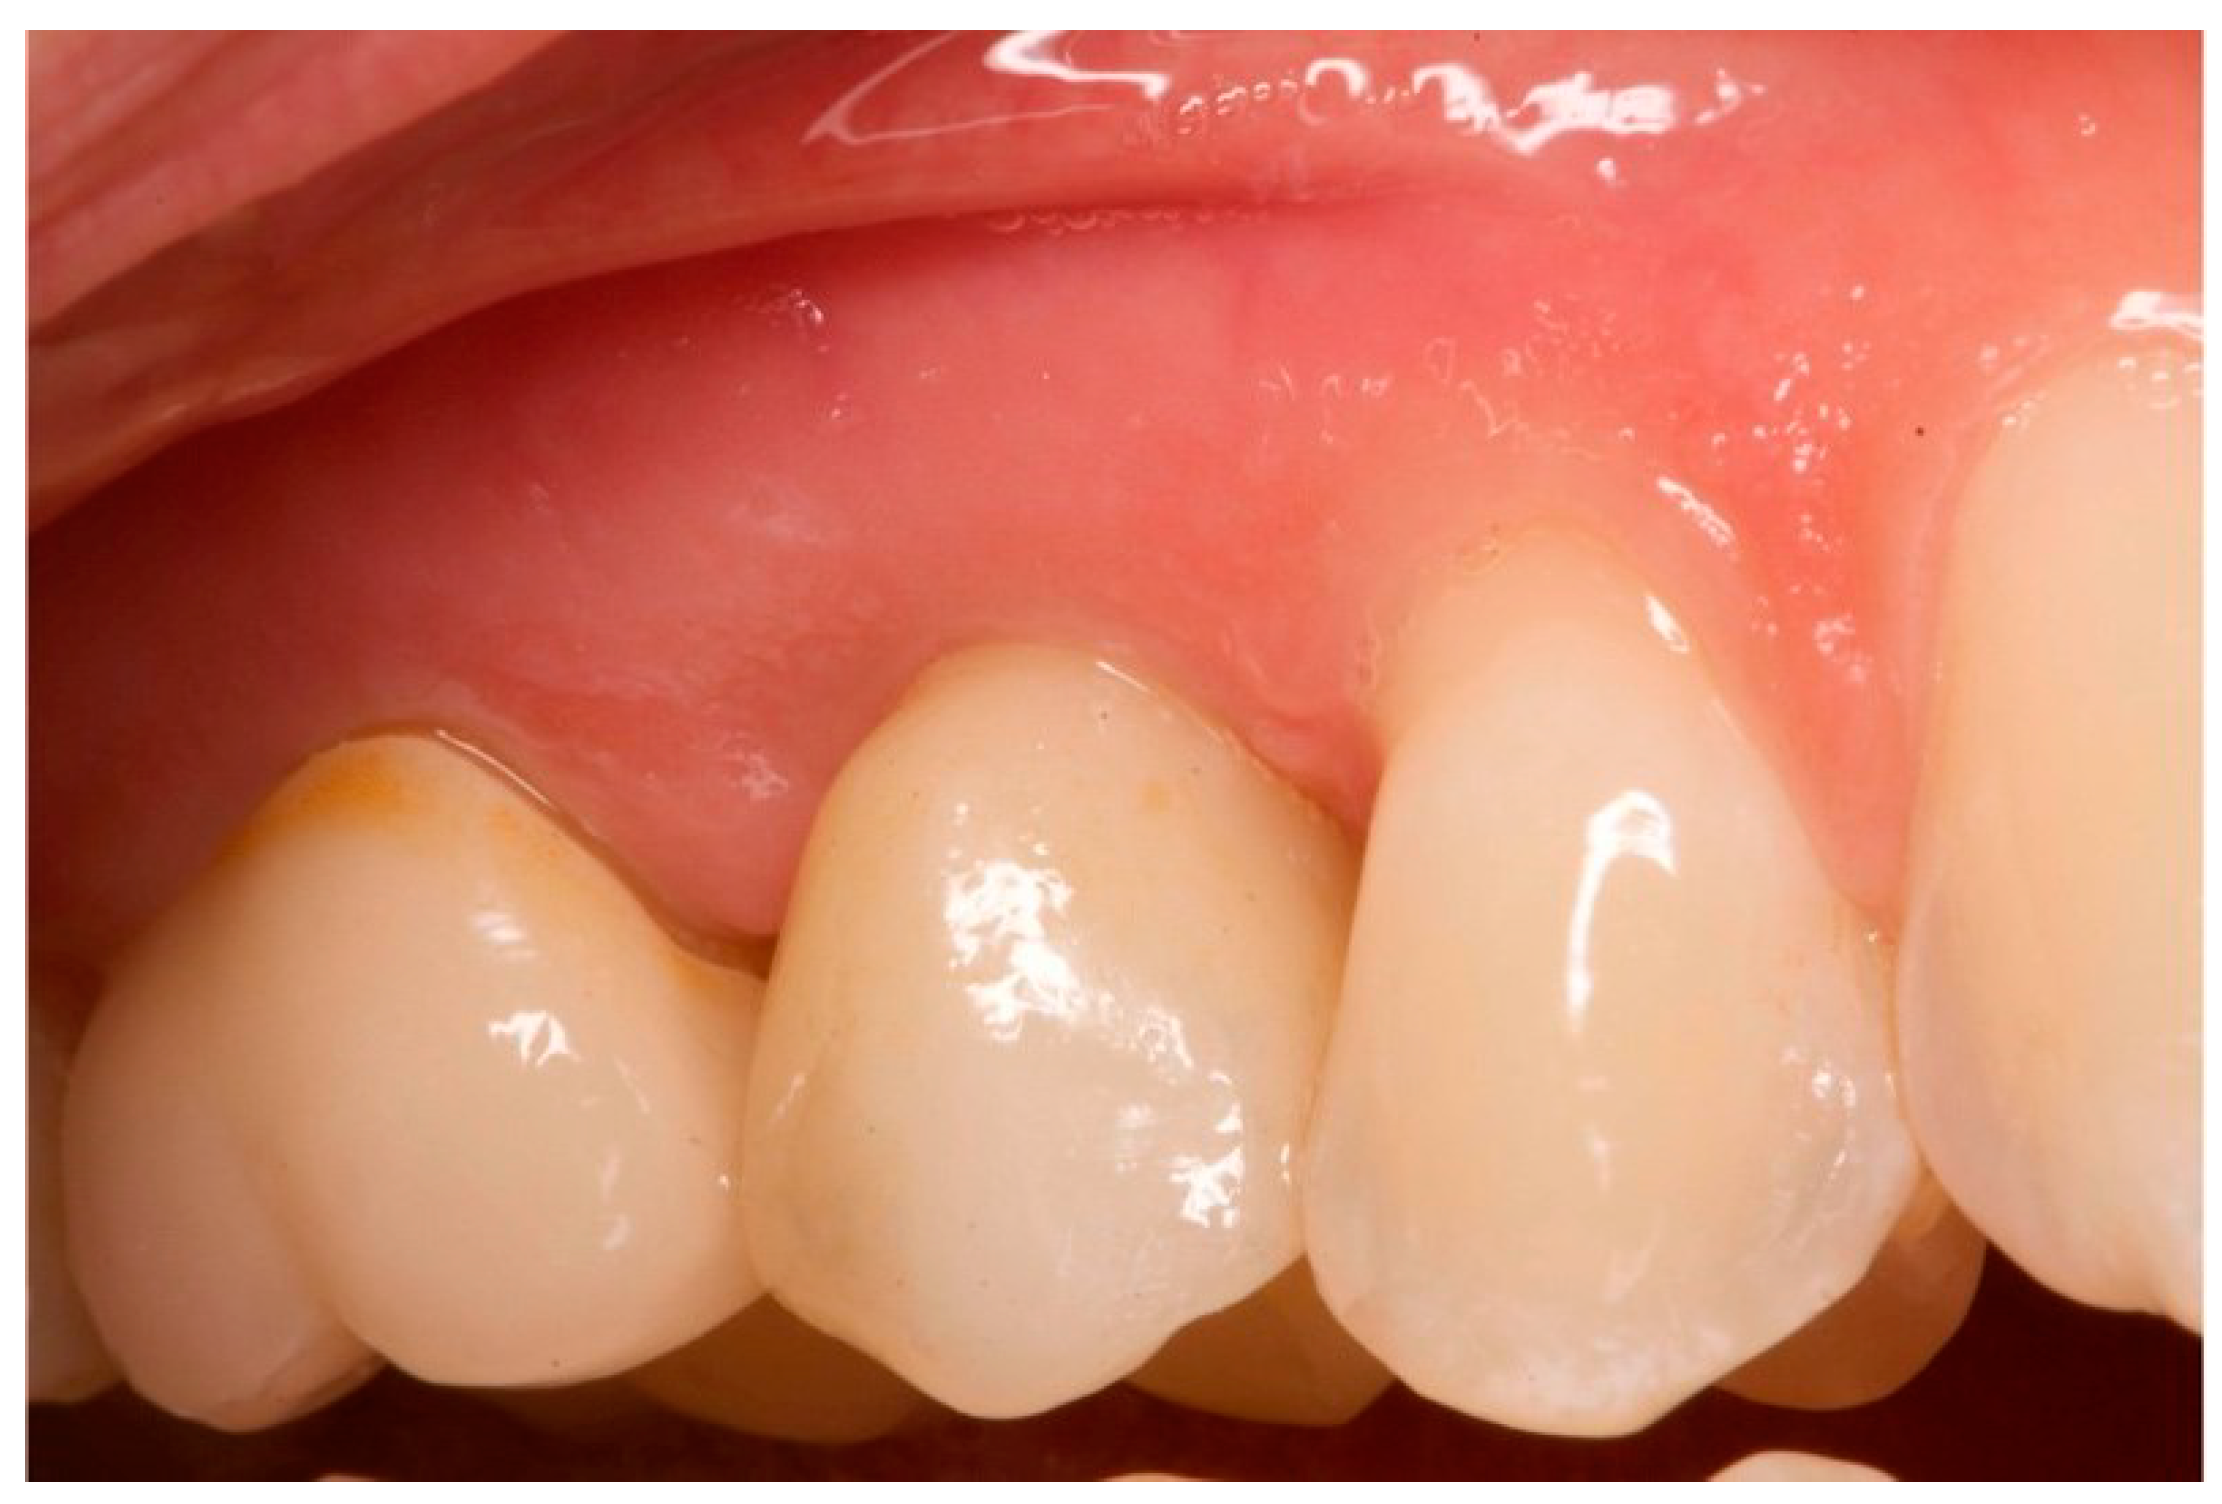

Figure 15.

One-year follow-up. Element 1.5.

Figure 16.

Five-year follow-up. Element 1.5 of the same patient.